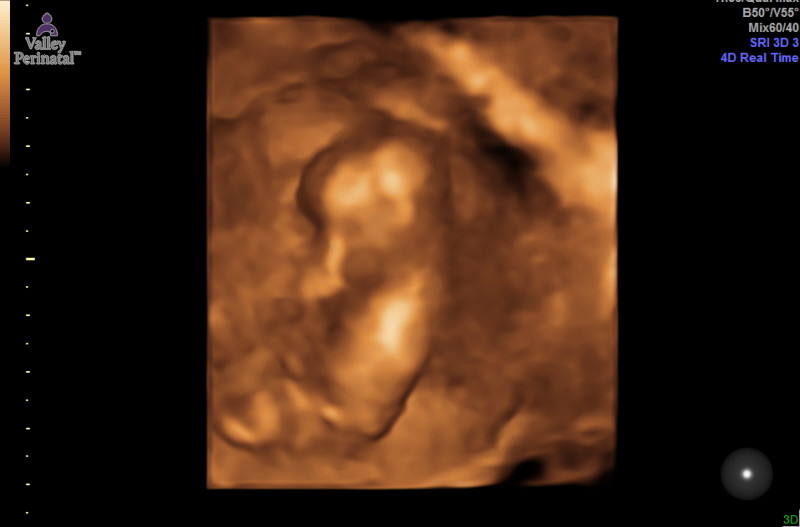

I had the gender experts do a prediciton they said girl, the Tech said girl too she thinks pink.. that is what I am hoping for I have 2 boys.. what do you guys think? I lso attatched one for skull theory from the same ultrasound? WE are goinga t 14 almost 15 weeks for an elective scan the picture was 12w 4d

Attachment 30219

The tech thought girl based on what she thought nub and the potty shot showed absolutely nothing

Hard to see the nub but i think girl.